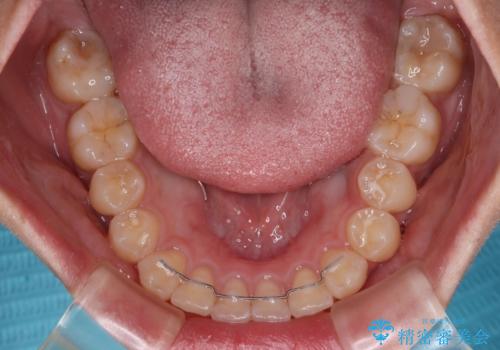

1年弱の短期間で、望み通りのスッキリとした口元に仕上げることができました。

- 11ヶ月